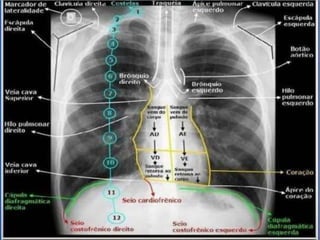

Radiografia de Tórax Normal

• Partes moles;

• Escápulas;

• Costelas;

• Coluna Vertebral;

• Campos Pulmonares;

• Hilos;

• Silhueta Mediastinal;

• Coração;

• Seios Costofrênicos;

• Seios Cardiofrênicos;

• Diafragma;

• Traqueia e Brônquios Fontes.

Radiografia de TóraxNormal • Partes moles; • Escápulas; • Costelas; • Coluna Vertebral; • Campos Pulmonares; • Hilos; • Silhueta Mediastinal; • Coração; • Seios Costofrênicos; • Seios Cardiofrênicos; • Diafragma; • Traqueia e Brônquios Fontes.